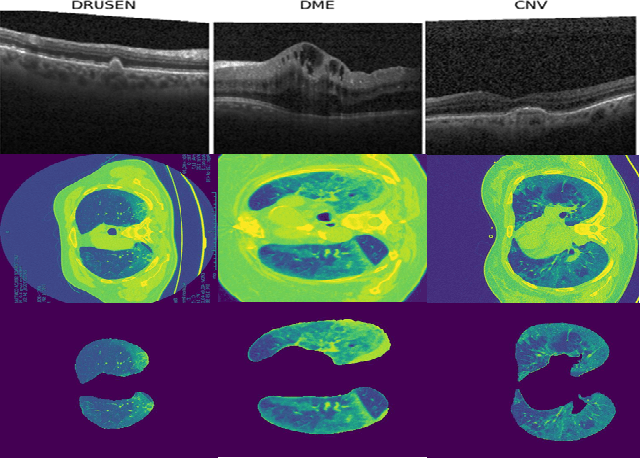

Abstract:Although automated pathology classification using deep learning (DL) has proved to be predictively efficient, DL methods are found to be data and compute cost intensive. In this work, we aim to reduce DL training costs by pre-training a Resnet feature extractor using SimCLR contrastive loss for latent encoding of OCT images. We propose a novel active learning framework that identifies a minimal sub-sampled dataset containing the most uncertain OCT image samples using label propagation on the SimCLR latent encodings. The pre-trained Resnet model is then fine-tuned with the labelled minimal sub-sampled data and the underlying pathological sites are visually explained. Our framework identifies upto 2% of OCT images to be most uncertain that need prioritized specialist attention and that can fine-tune a Resnet model to achieve upto 97% classification accuracy. The proposed method can be extended to other medical images to minimize prediction costs.